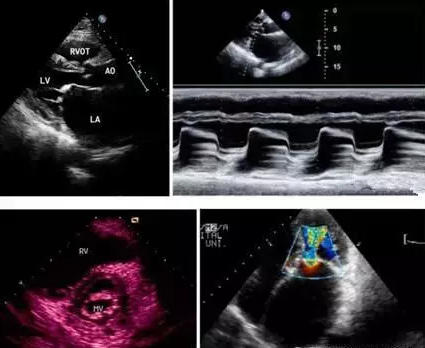

心血管超声

贯穿生命始终的心血管超声:先天性心脏病(胎儿期、小儿期、成人期)、冠心病、心脏瓣膜病、心力衰竭、血管......